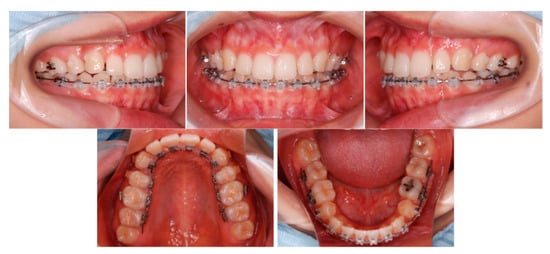

6.5. Treatment Results

6.6. Case Summary